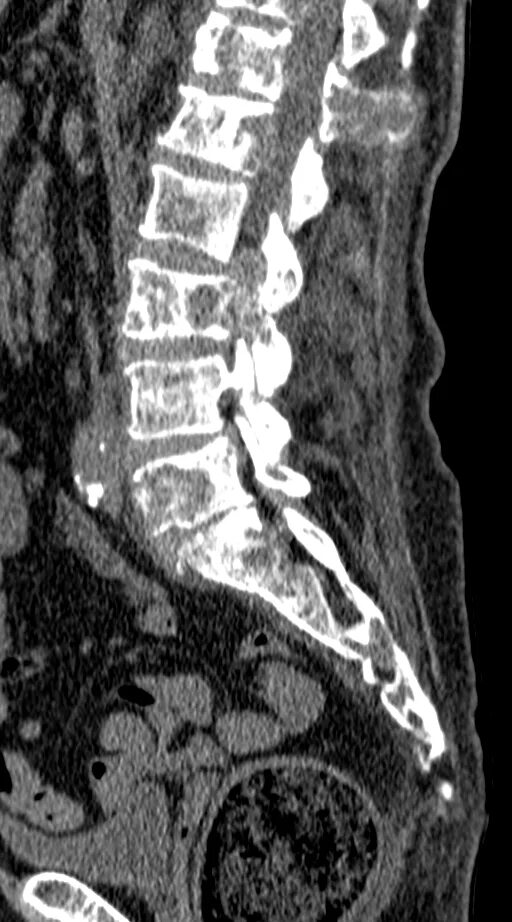

Метастазы в матке